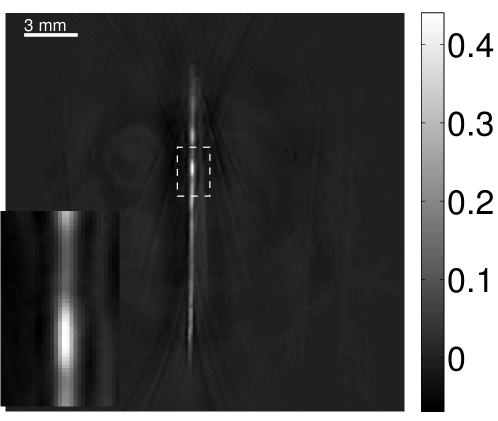

Figure 11 displays images of the needle phantom reconstructed by use of the simple backprojection method [BM2003]. Figures 12 and 13 display the images reconstructed by use of the conventional iterative method and VP algorithm, respectively.

Figures 12 and 13 show that the width of the needle in the reconstructed image increases as the regularization parameter increases for both the conventional iterative method and the VP algorithm. The images reconstructed by use of the VP algorithm appear to have a reduced noise level compared to the images reconstructed by the backprojection and conventional iterative methods, regardless of the choice of the regularization parameter values. The profile plots corresponding to these three methods are shown in Figure 14. Since the image of the coefficient vector and the EIR are recoverable only up to a multiplicative constant, every profile was normalized for comparison. These plots demonstrate that the image reconstructed by use of the VP algorithm possessed a more uniform background than those obtained by the backprojection and the conventional iterative methods.